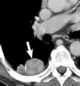

Pleural mesothelioma

Mesothelioma is a type of cancer that develops from the thin layer of tissue that covers many of the internal organs (known as the mesothelium). The most common area affected is the lining of the lungs and chest wall. [Source: Wikipedia ]